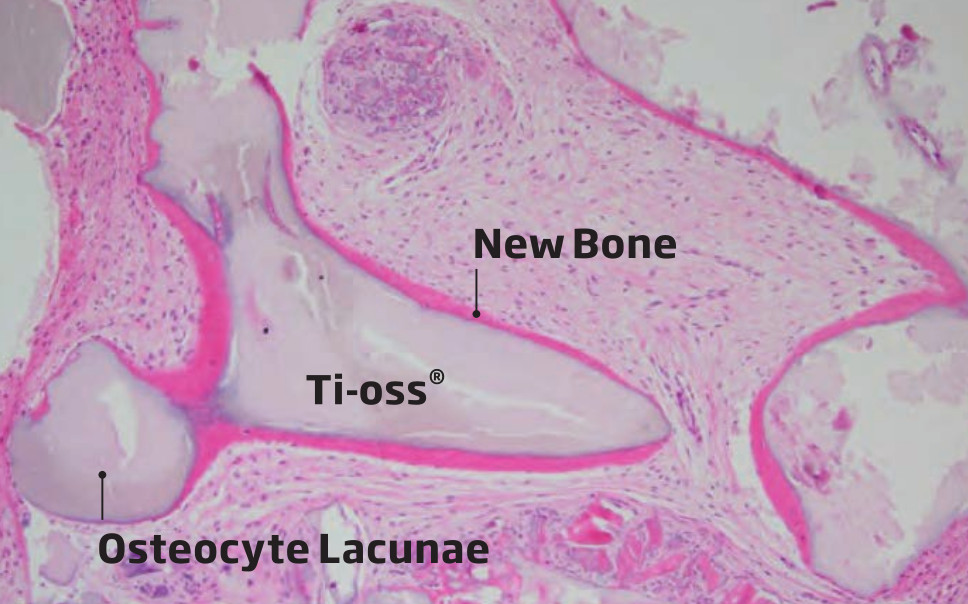

Osteoprzewodzący charakter powierzchni Ti-oss® oceniono na podstawie próbek biopsyjnych.

Konsekwentne tworzenie się nowej tkanki odnotowano w kilku różnych przypadkach klinicznych, dzięki czemu jesteśmy w stanie osiągnąć, przewidywalność i niezawodność procesu regeneracji we wczesnych etapach tworzenie się nowych struktur.

Obserwacja Osteocyte Lacunae

Research Report date: May, 2012 • Kim, Sun Young, D.D.S. Prosthodontist • Suplant Dental ClinicSeoul, Korea

Wyniki biopsji po 3 miesiącach